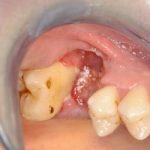

Patient 43 Jahre, männlich, Nichtraucher mit unauffälliger Allgemeinanamnese stellte sich am 20.01.2006 erstmalig zur Routineuntersuchung vor. Diese ergab neben einem Gesamtsanierungsbedarf unter anderem auch die Nichterhaltungswürdigkeit des Brückenpfeilers 45. Nach intensiver Aufklärung über Therapieoptionen und Erstellen eines Behandlungsplanes, erfolgte nach zwei Initialsitzungen zur Mundhygienemotivation zunächst die konservierende und parodontologische Vorbehandlung. Am 09.10.2006 wurden die Zähne 18, 45 und 48 in Lokalanästhesie entfernt. Der Operationssitus offenbarte eine knöcherne Dehiszenz des Zahnes 45 bis zum Apex und einen in vestibulo-oraler Richtung stark atrophierten Kieferkamm regio 46.